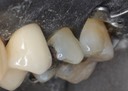

Joe Cha #19 pre-op

Joe Cha #18 pre-op